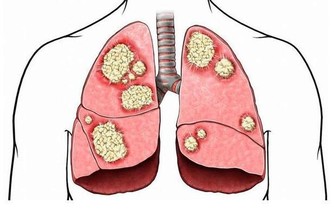

最易退化的3個關節

關節遍布人體的軀幹及四肢,舉凡活動度大、承受力量小的部位,較不易受傷退化,

例如肩膀;至於活動度小、負重量大的關節如膝關節、脊椎及髖關節,最容易受傷、退化。

膝關節尤其是人體所有關節、軟骨構造中最為複雜的部位,

包括髕骨、大腿股骨、小腿脛骨、兩個半月狀軟骨及四條韌帶,活動機轉相當複雜。

加上膝關節必須承受人體全部或數倍的重量,

加上日常跑、跳、上下樓梯、背負重物、穿高跟鞋等因素,

膝蓋的受力更大,是全身關節中最容易退化的部位。